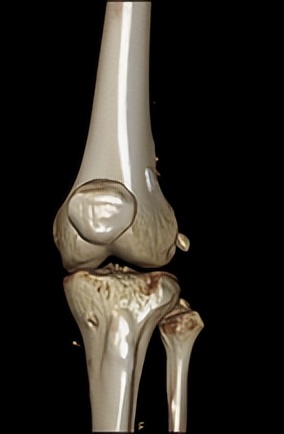

△术后CT复查可见悬吊钢板和挤压钉位置良好(左图),MRI显示重建的前交叉韧带(右图)

手术中,何河北医生采用微小切*技口**术,取出小张膝盖同侧的半腱肌,将肌腱编制后,再在关节镜下,于股骨以及胫骨建立骨隧道,使用可调节袢将肌腱悬吊在股骨隧道侧,最后用可吸收挤压钉将胫骨侧固定。

这次微创手术最大切口2cm,最小切口仅为0.5cm。